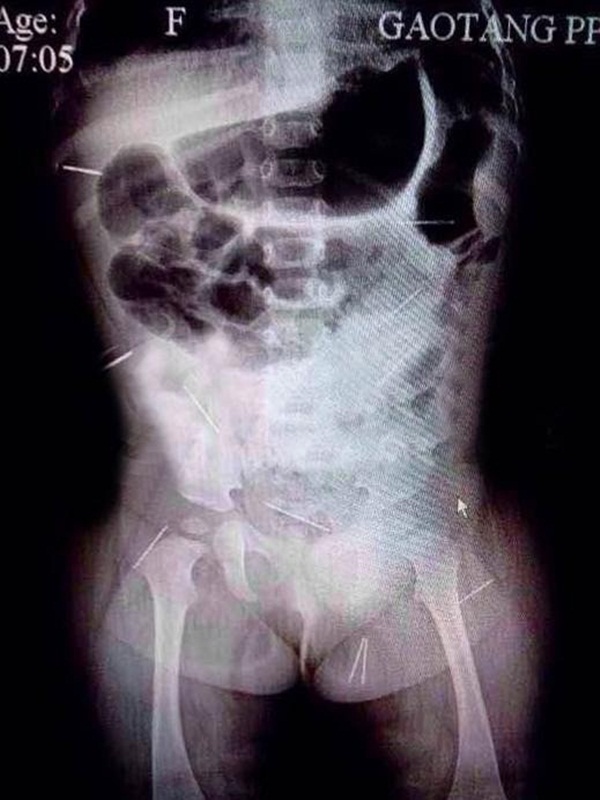

12 cây kim năm quanh cơ thể của Phạm Tử Huyên.

Nhìn vào kết quả chụp X-quang, vợ chồng cô suy sụp khi phát hiện có 12 cây kim với đủ loại hình dáng đâm vào cơ thể của Tử Huyên. Trong hình chụp có thể thấy được, những chiếc kim này được phân phối ở mông, khoang bụng, xương chậu và những bộ phận khác. Nhận thấy tình hình không còn là vấn đề sức khỏe thông thường, bố của Tử Huyên lập tức báo cảnh sát. Do điều kiện hạn chế ở bệnh viện huyện nên Tử Huyên được chuyển đến Bắc Kinh để tiến hành phẫu thuật lấy 12 cây kim ra khỏi cơ thể bé gái.